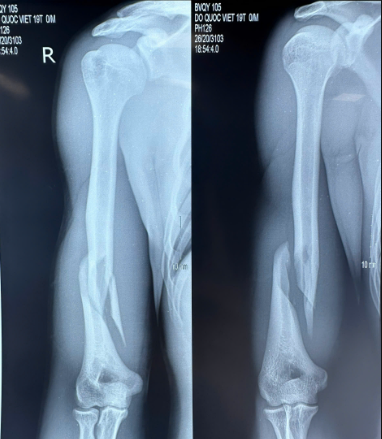

Bệnh nhân nam, 19 tuổi, nhập viện trong tình trạng đau chói và mất vận động cánh tay sau khi vật tay. Tại khoa Chấn thương Chỉnh hình, Bệnh viện 19-8, người bệnh được tiếp nhận và thăm khám khẩn trương. Qua đánh giá lâm sàng và phim XQ của người bệnh, BSCKII Đỗ Việt Sơn (phó trưởng khoa) nhận định đây là trường hợp gãy phức tạp 1/3 dưới xương cánh tay, đồng thời loại trừ tổn thương thần kinh quay – một biến chứng thường gặp trong loại chấn thương này.

Hình 1. Phim XQ của bệnh nhân. Gãy phức tạp 1/3 dưới xương cánh tay phải (ổ gãy điển hình của tổn thương xương cánh tay do vật tay).